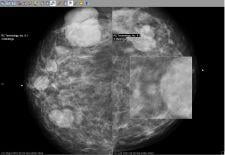

Candelis Inc. will showcase its recently FDA cleared ImageGrid Mammography Web Viewer and ImageGrid Radiology Web Viewer, which are now part of the ImageGrid RIS/PACS Appliance technology suite, at SIIM 2008.

The ImageGrid Mammography Web Viewer and Radiology Web Viewer are diagnostic tools aiming for timely access to medical imaging studies from anywhere and at any time to improve patient care. Both viewing applications are highly scalable and designed to

accommodate multiple concurrent users without the need to invest in additional servers, said the company. As a multi-modality visualization solution, the viewers allow radiologists to view all relevant prior studies from one workstation.

For hospitals with specialty imaging departments, the ImageGrid RIS/PACS Appliance provides immediate access and diagnostic viewing capabilities from any workstation on the network. As a thin-client application, the ImageGrid Web Viewers do not require installation of costly software on every workstation on the network or at a physician’s remote workstation.